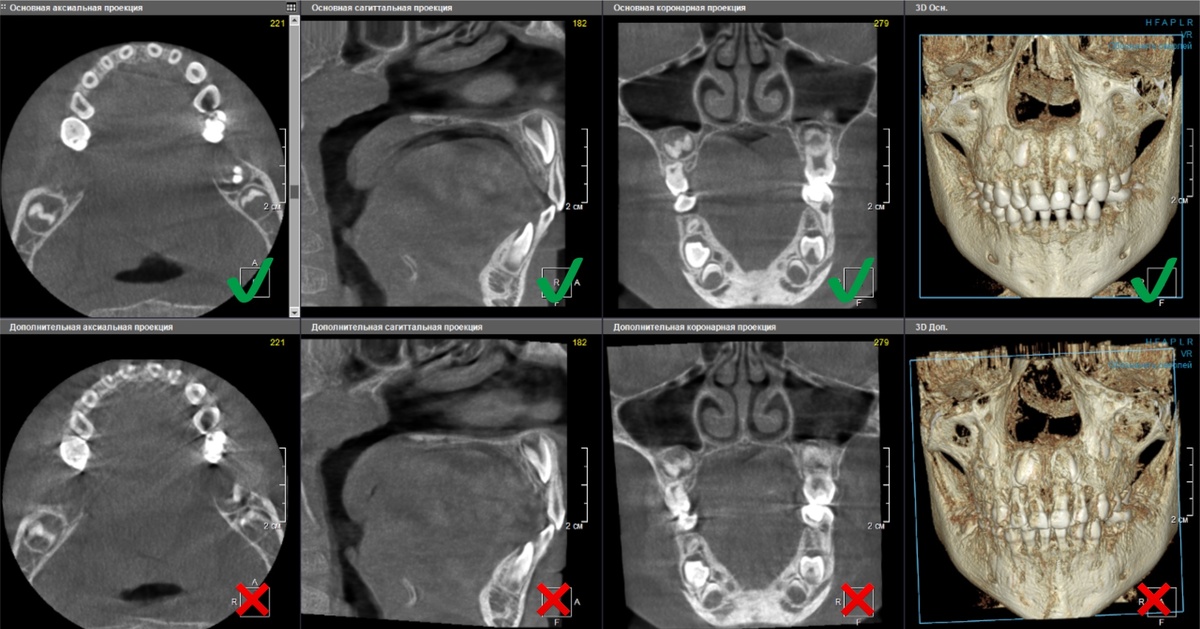

Ниже приведены примеры артефактов на 3D-снимках:

Нечеткие контуры корневых каналов, двойные контуры анатомических структур свидетельствуют о движении во время сканирования

Слева - хороший снимок, справа - звездочка вместо четкого круглого канала